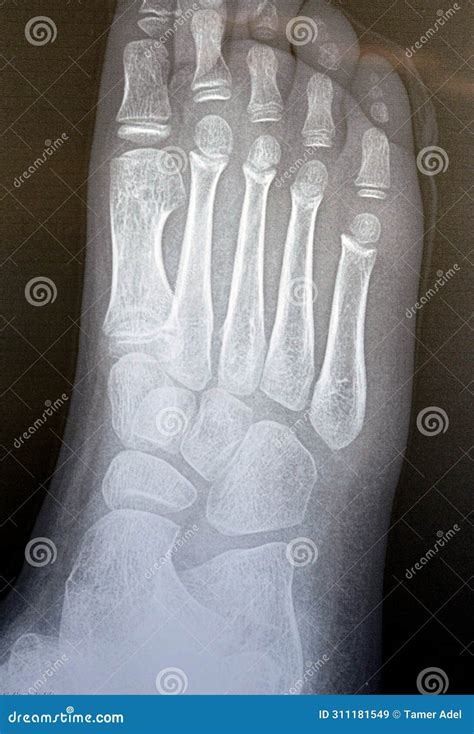

Interpreting a Normal Foot Xray involves a detailed examination of the images by a radiologist or orthopedic specialist. Key areas of focus include:

• Bone density and structure

• Joint spaces and alignment

• Presence of fractures or dislocations

• Soft tissue abnormalities

• Signs of arthritis or other degenerative conditions

In a normal Xray, the bones should appear smooth and continuous, with no visible fractures or dislocations. The joint spaces should be uniform, and there should be no signs of bone spurs or other abnormalities.